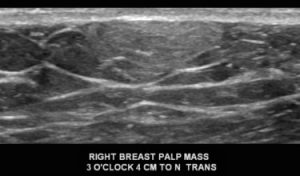

With the mammogram appearing negative, a diagnostic ultrasound was performed. What is the diagnosis?

Explanation: This is a circumscribed, oval, hyperechoic mass, which is consistent with a lipoma. They have the same imaging appearance in males and females. They may appear as circumscribed fat-containing masses on the mammogram, particularly if the patient has a lot of fibroglandular tissue. Since this male’s breast is composed predominantly of fat density, the lipoma cannot be easily discerned on the mammogram. On ultrasound, a lipoma (arrows) is either isoechoic or slightly hyperechoic to the surrounding subcutaneous fat (*). Lipomas are benign and when correctly identified on imaging, they do not require further follow-up.

D. Lipoma; BI-RADS 2 (Benign)